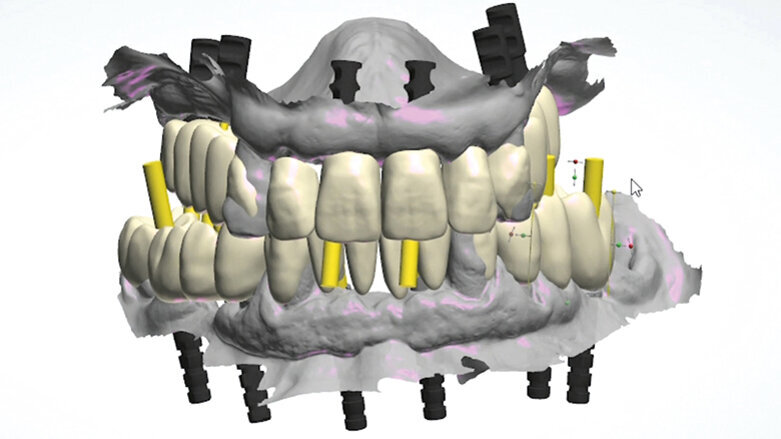

Pro Arch od společnosti Straumann je koncept, který zahrnuje různá léčebná řešení pro zcela bezzubého pacienta. Cílem je poskytnout předvídatelnou, reprodukovatelnou a co nejjednodušší léčbu, která obnoví orální zdraví pacientů a následně dramaticky zlepší kvalitu jejich života. Možnost okamžité rehabilitace ve stejný den pomocí provizorní náhrady nabízí maximální kvalitu léčby a spokojenost pro dentální tým i pro pacienta. Cílem ošetření s okamžitě zatíženou fixní náhradou nesenou implantáty je zlepšit pacientovu kvalitu života tím, že poskytuje funkci a estetiku ještě před dosažením plné oseointegrace implantátů.

Díky plně digitálnímu pracovnímu postupu, který začíná použitím intraorálního skeneru, je pracovní tým schopen nabídnout přesné individuální ošetření. Kompletně digitální postup ošetření – od digitálního otisku až po konečnou protézu, může být považován za novou formu implantologie, při níž jsou různé prvky léčby optimalizovány pro vysokou úroveň výsledku v rámci moderní stomatologie.

S ohledem na tento cíl jsme v centu i2 Implantología (Madrid, Španělsko) vyvinuli řadu řešení a protokolů pokrývajících různé klinické situace u plně bezzubých pacientů a založili jsme je na klasických implantologických principech s cílem získat předvídatelné a reprodukovatelné výsledky s použitím intraorálního skeneru jako stěžejního prvku. Naše protokoly zahrnují použití určitých prvků (adekvátní implantační systém, Osstell, atd.) a zevrubné protokoly pro skenování, chirurgické a protetické procedury a laboratorní práce, včetně výroby a údržby provizorních náhrad.

V níže uvedeném případě uvádíme protokol i2 Standard. Tento protokol může být aplikován u pacientů, kteří vyžadují odstranění terminální dentice. Ve výsledku to zahrnuje extrakce vybraných zubů, zavedení implantátů, intraorální digitální otisky, návrh a výrobu provizorní náhrady z PMMA s jejím odevzdáním pacientovi ve stejný den.

Je důležité poznamenat, že náš plně digitální protokol pro dosažení finální náhrady je založen, pokud je to zapotřebí, na vytvoření různých po sobě následujících dočasných náhrad, dokud není dosaženo oseointegrace. Iniciální návrh upravíme (a vytvoříme další provizoria) vždy plně digitálním postupem, abychom získali konečný návrh provizorní náhrady, která splňuje funkční a estetické parametry pacienta. Informace poskytnuté tímto finálním návrhem budou zkopírovány do konečného protetického návrhu. Vyškolený dentální tým, klinika a laboratoř jsou stěžejní podmínkou.

Cílem bylo okamžitě zatížit implantáty šroubovanou provizorní náhradou. Aby toho bylo dosaženo, byly naplánovány strategické extrakce při dočasném zachování některých zubů jako klíčových prvků, které při intraorálním skenování determinují pacientovu estetiku, výšku skusu a protetický oblouk. Rozhodli jsme se provést minimálně invazivní chirurgii s technikou flapless tam, kde to je možné, aby se zabránilo tomu, že by mobilizované tkáně mohly ovlivnit intraorální skenování. Pro rekonstrukci bylo naplánováno zavedení šesti implantátů Straumann Bone Level Tapered, Roxolid, SLActive se šroubovanými abutmenty (SRA).